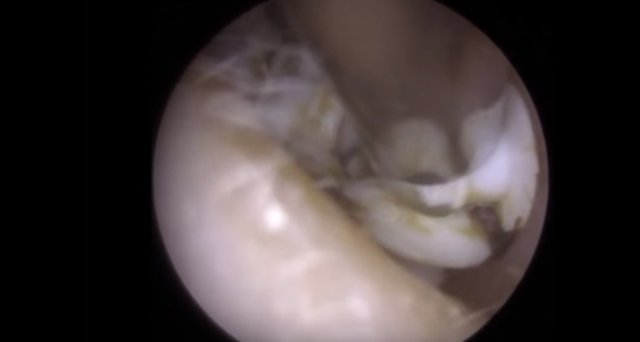

30 yıl boyunca geçmeyen bir baş ağrısı ile yaşayan bir kişi gittiği doktoru şoke etti. Yıllarca baş ağrısı çeken 59 yaşındaki adamın yaşadıkları kan dondurdu. Adamın kafasından öyle bir şey çıktı ki, doktorlar bile şaştı kaldı. İşte şoke eden olayın detayları...